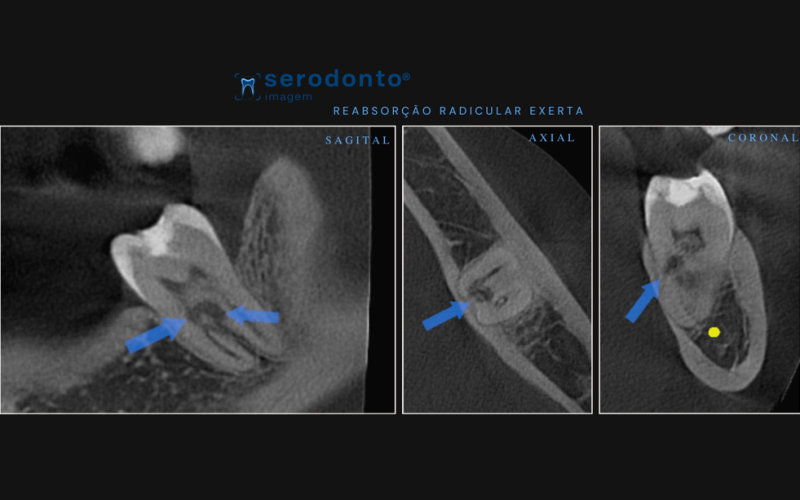

A reabsorção radicular externa é uma condição que afeta a estrutura da raiz do dente, resultando na perda óssea e, em muitos casos, comprometendo a estabilidade do dente afetado. Detectá-la precocemente é essencial para evitar a perda dental. A tomografia de alta resolução tem se mostrado uma ferramenta indispensável na avaliação precisa dessa condição.

A tomografia computadorizada (TC) oferece imagens tridimensionais detalhadas que permitem identificar e avaliar a extensão da reabsorção radicular externa. Com a alta resolução da tomografia, os dentistas conseguem visualizar com precisão até as áreas mais profundas da raiz, possibilitando um diagnóstico mais assertivo.